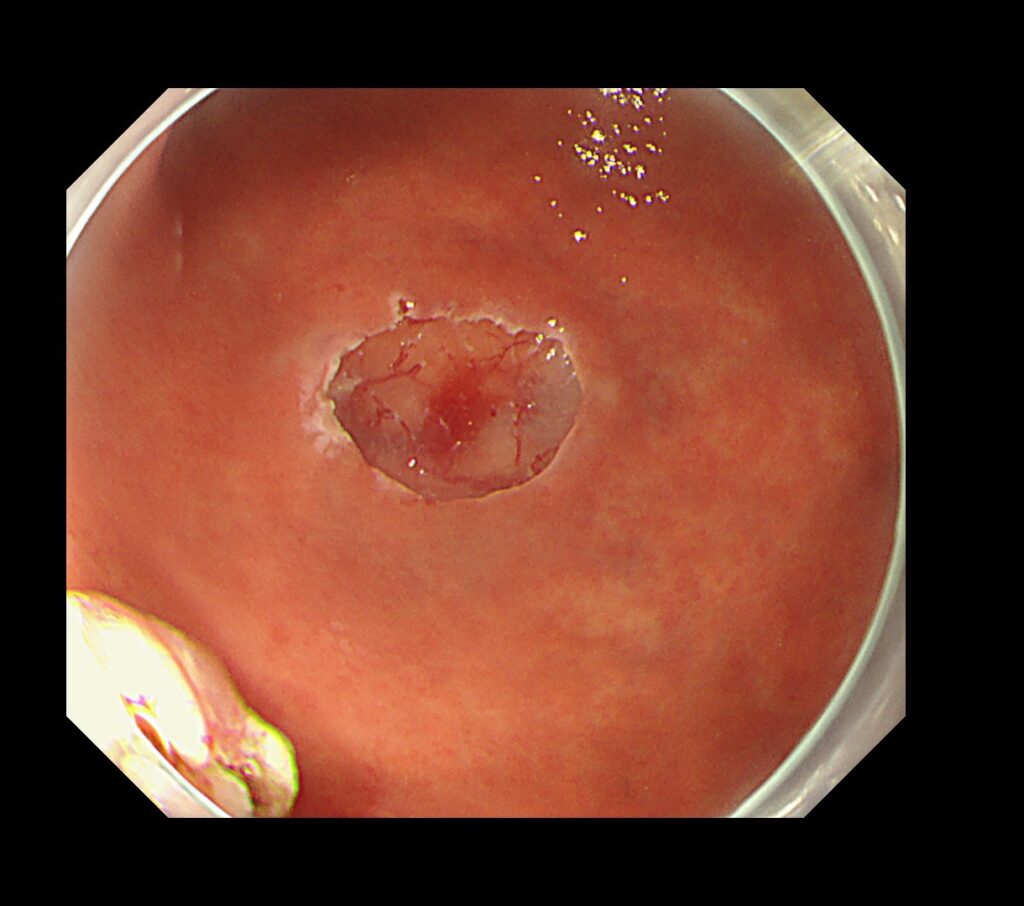

NBI拡大観察モード(倍率を上げて、癌の局在と範囲、組織型を確定させるモード)で、切除範囲をマーキングします。

マーキングから、病変摘出までわずか”3分”で終了。

胃癌のESDも入院せず、日帰りの時代が到来したと考えております。